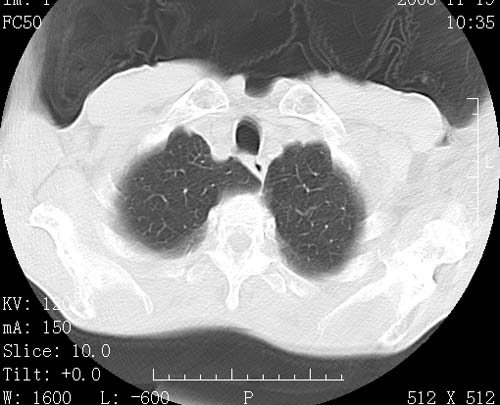

术前查体,双肺部结节是转移?结核?请点评

1)符合食管癌表现。2)两肺及纵隔淋巴结多发性转移瘤。3)左肺上叶舌段及两肺下叶炎症感染。

1)符合食管癌表现。2)两肺及纵隔淋巴结多发性转移瘤。3)左肺上叶舌段支气管扩张伴感染.

食管癌伴双肺转移,评述:肺部毛细血管网丰富,全身血液均快速流经肺部,癌细胞容易过滤定植,形成转移瘤,影象特点为以毛细血管末梢为中心的结节灶,边缘光滑锐利,少见有中心空洞着,不同来源的转移瘤可有各自特点,如甲状腺癌为双肺弥漫性微结节,本例有原发灶,双肺影象灶典型,左肺舌段条带状网格样伴胸膜天幕征,可视为癌性淋巴管炎。

符合食管癌表现。两肺及纵隔淋巴结多发性转移瘤。双肺还有支扩表现.

1)符合食管癌表现。2)两肺及纵隔淋巴结多发性转移瘤。3)左肺上叶舌段支气管扩张伴感染

1)符合食管癌表现。2)两肺及纵隔淋巴结多发性转移瘤。3)左肺上叶舌段感染并支扩。

左肺舌段有斑点钙化灶,能否说明是结核而不是转移?如果是转移将放弃手术改成化疗,如果是结核将考虑择期手术